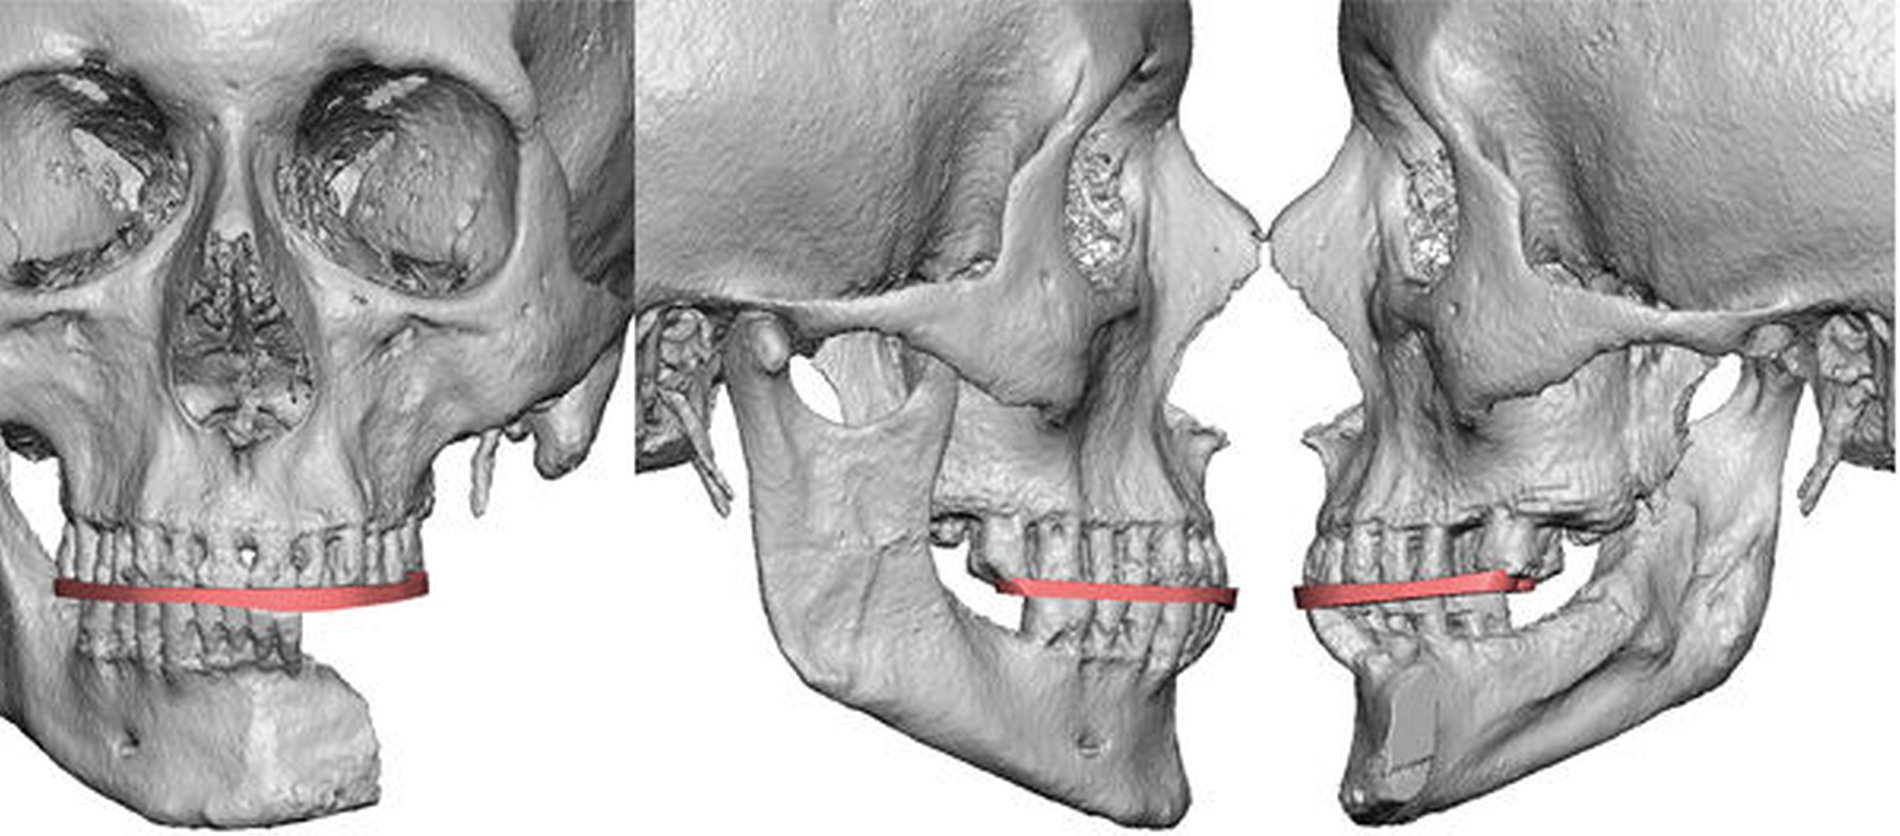

Abbildung 2 zeigt in der CT die Ausgangssituation mit frakturierter Rekonstruktionsplatte und massiver Okklusionsstörung durch die Innenrotation der Mandibula.

Die CT-Daten wurde in die Software der Firma 3D Systems (3D Systems, Littleton, USA) eingelesen und aufbereitet. Dadurch ist es möglich, relevante Areale zu segmentieren und bei der Planung virtuell frei zu positionieren. Dies kann in Abbildung 3 gut nachverfolgt werden. Die rotierte Mandibula wurde in ihre ursprüngliche Position und somit die Restbezahnung in Okklusion mit dem Oberkiefer gebracht.

Die neue Okklusion wird postoperativ mittels intermaxillärem Splint gesichert (Abbildung 4). In den Folgeschritten werden die Resektionsgrenzen festgelegt und die notwendigen Fibulasegmente angepasst (Abbildung 5).